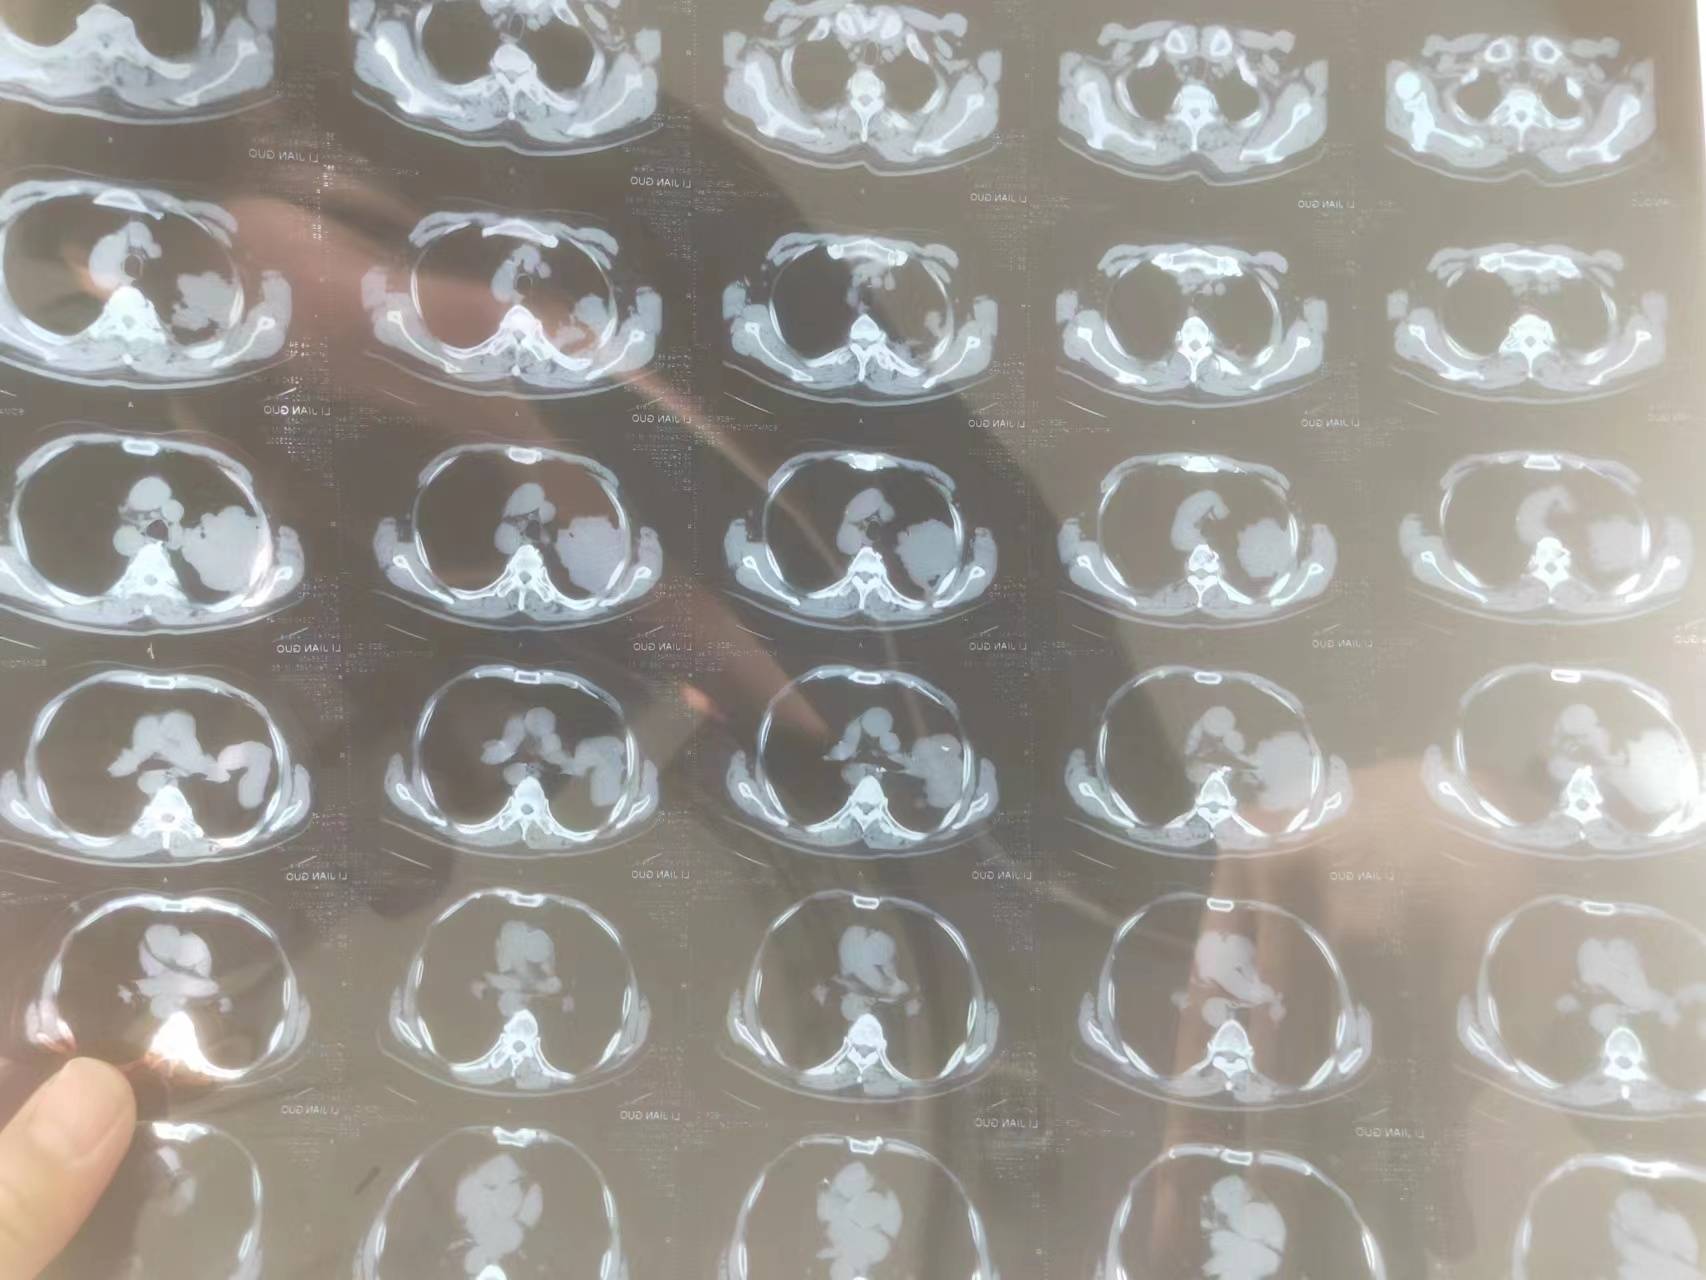

手术目前就不用考虑了,至少是3期了,还是寻求化疗和靶向治疗

局部晚期,有转移了肯定不能直接手术了,一般可以这样理解,就是气管镜够得到的话就是中央型(当然有些情况是肿瘤太大可以够到,但是实际附着区域可能在周围?),血管分布就是从心脏大血管向两肺分支,可以去搜下肺血管的解剖图,结合肿瘤部位自行想象这个距离(这么大的肿瘤一般都靠近大血管的,很考验外科医生的水平